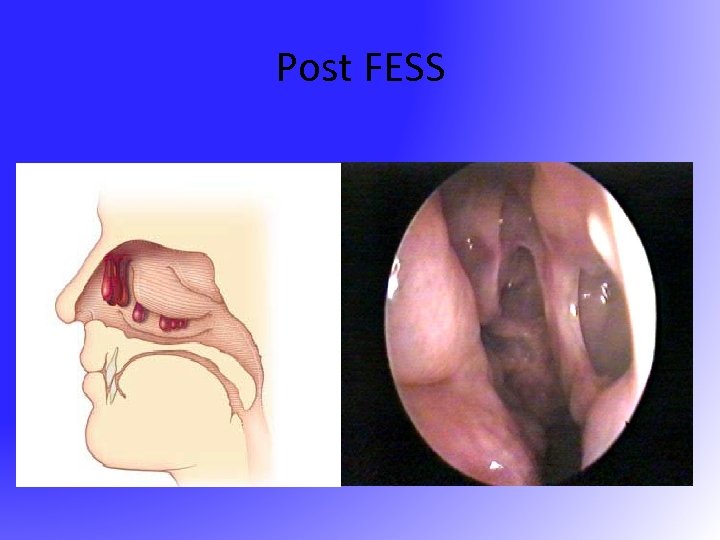

Post FESS

Post FESS